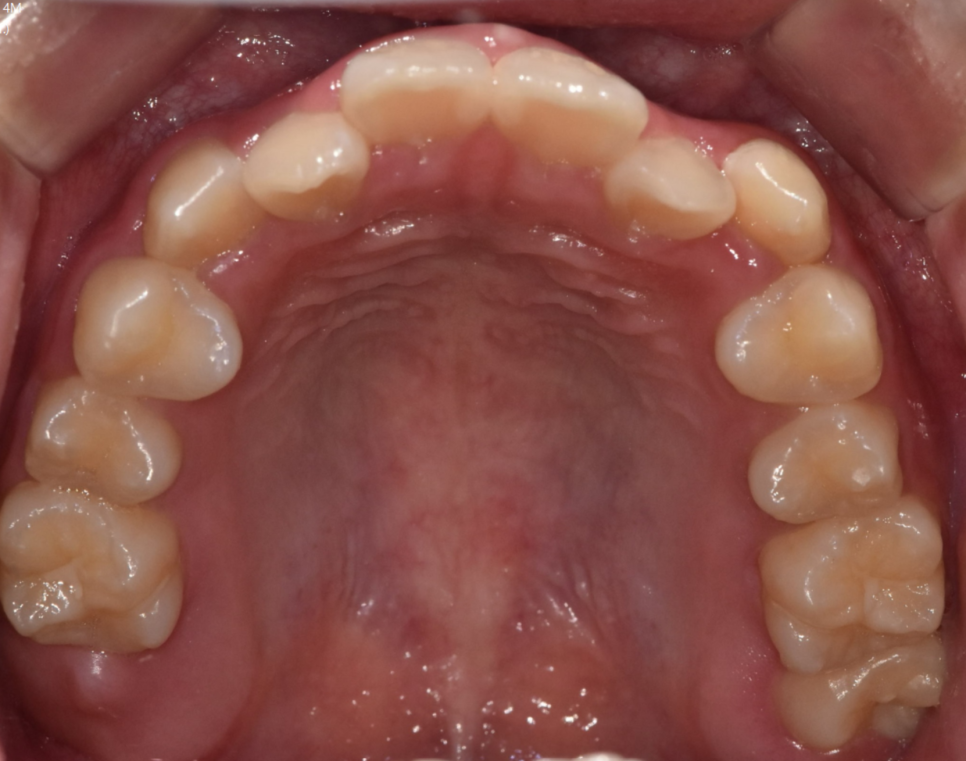

가장 이상적인 것은

교정 장치를 부착하기 전에 치료하는 것이 좋습니다.

250120 깨끗한 환경에서는 치료도 충치 발견도 쉽습니다 .